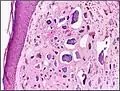

![]() صورة مجهرية للكلاس الجلدي. يظهر التكلس باللون الأرجواني (أسفل الصورة). باستخدام صبغة الهيماتوكسيلين والأيوسين. صورة مجهرية للكلاس الجلدي. يظهر التكلس باللون الأرجواني (أسفل الصورة). باستخدام صبغة الهيماتوكسيلين والأيوسين. | |

الكلاس الجلدي في أنسجة بشرية.